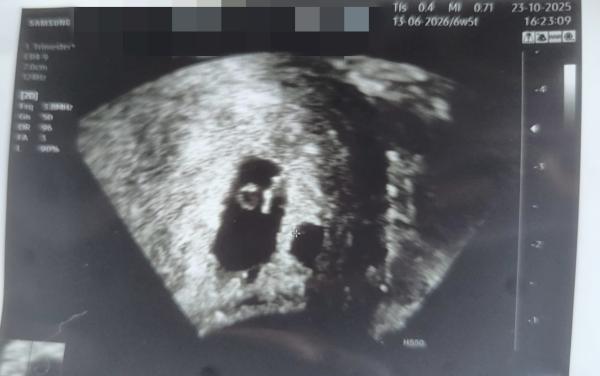

Ich Frage mich seid dem letzten Frauenarztbesuch ob das zwei Fruchthöhlen sind, aber wenn es zwei sind sieht man in der kleineren leider nichts, kann sich da noch was entwickeln? Das Bild ist von 6W5T  Danke für eure Antworten :) vielleicht war es ja bei der ein oder anderen Mama auch so